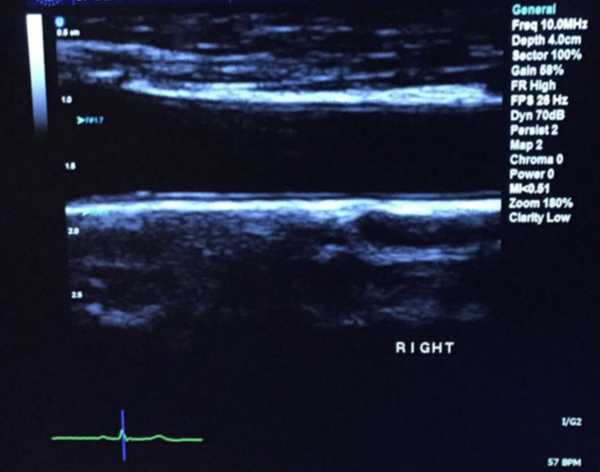

Лікар проводить ультразвукове дослідження сонної артерії пацієнта. (Зображення: simon2579 через Getty Images)

Екран ультразвукового дослідження, що показує 2D-зображення сегмента загальної сонної артерії. Центральна чорна область – це канал усередині сонної кровоносної судини, а більш чіткі шари з кожного боку цього центрального каналу – це стінки артерії. На периферії зображення показано м’які тканини, що оточують артерію.

Спочатку дослідники провели ультразвукове дослідження сонних артерій 135 людей з тяжким пародонтитом, щоб встановити базовий рівень товщини. Вони також виміряли, наскільки розширювалися артерії при збільшенні кровотоку — показник функціонування кровоносних судин — і взяли зразки крові, щоб точно визначити маркери запального та оксидативного стресу. Усі особи були здоровими, окрім захворювань ясен.